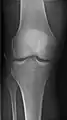

• Elbow - AP and Lateral. Radial head projections available on request

• Knee - AP and Lateral. Intra Condular projections on request